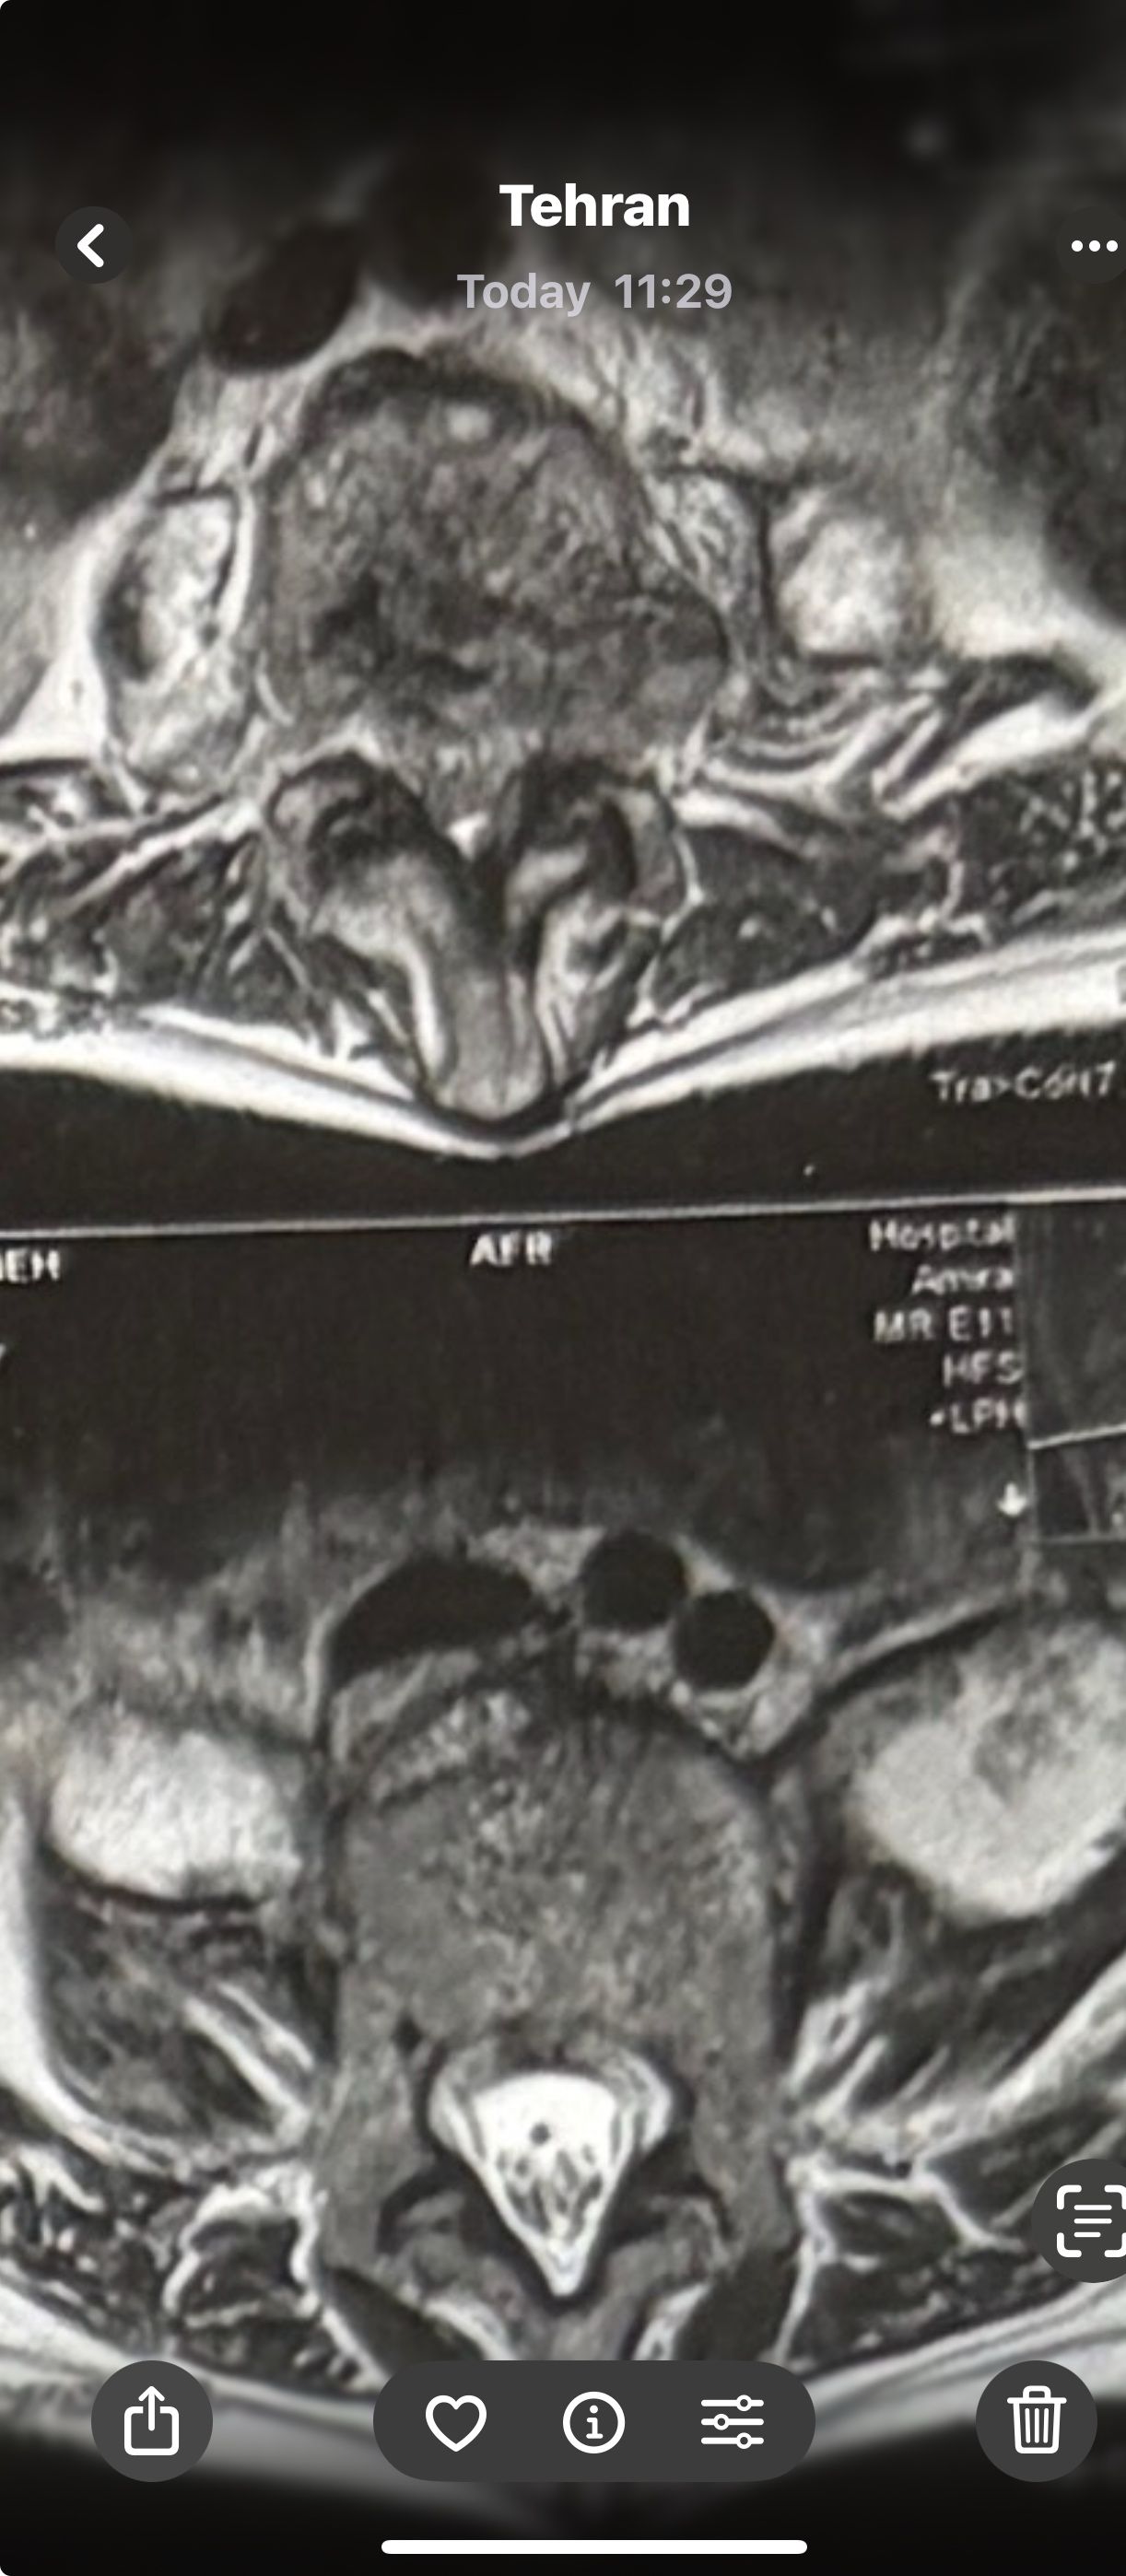

46 years old female patient presented to my clinic yesterday june 1/2025 with LBP and radicular L leg pain for several months which hasn’t responded to physio 2 neurosurgeons have visited her and didn’t suggest any surgery Neurological exam was unremarkable please see her mri/ emg/ncv and her huge tarlov cyst and possible L IVF L4-5 hyperbulge I ordered sacrum mri and ct scan and new emg/ncv and asked her with her sacral Ct scan and MRI first sees another two famous neurosurgeons and see if that large cyst is the reason for her pain if not i can work on her L4-S1 area Do you think her radicular pain can originate from her large cyst in sacrum? Do you consider surgery and removing her sacral cyst?